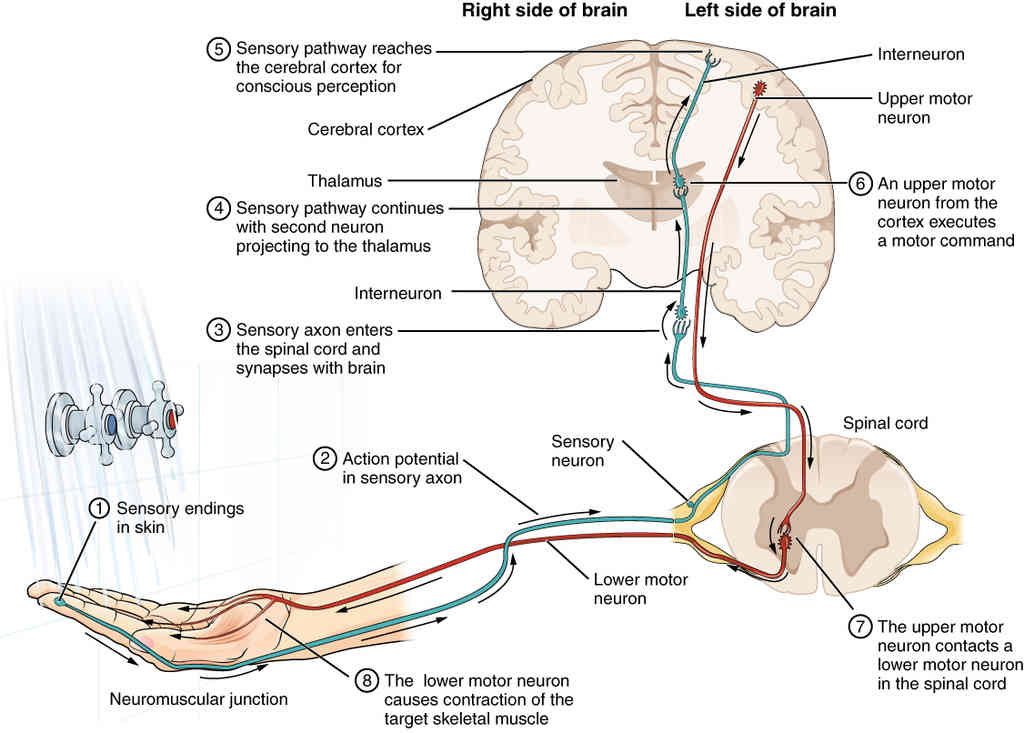

This page is under construction. For now, it is just a resource of the images found in the OpenStax Anatomy and Physiology Handbook. It wil slowly change into a revision tool. Each slide has a number. Use this to refer to the slide. When completed, it will have an unlabelled section, with labelled slides in parallel. On the unlabelled slides, write your answer and use the labelled slide to assess yourself. Keep track by also noting the number on each slide. Improvement at each attempt is important, more so than full marks on a first attempt.